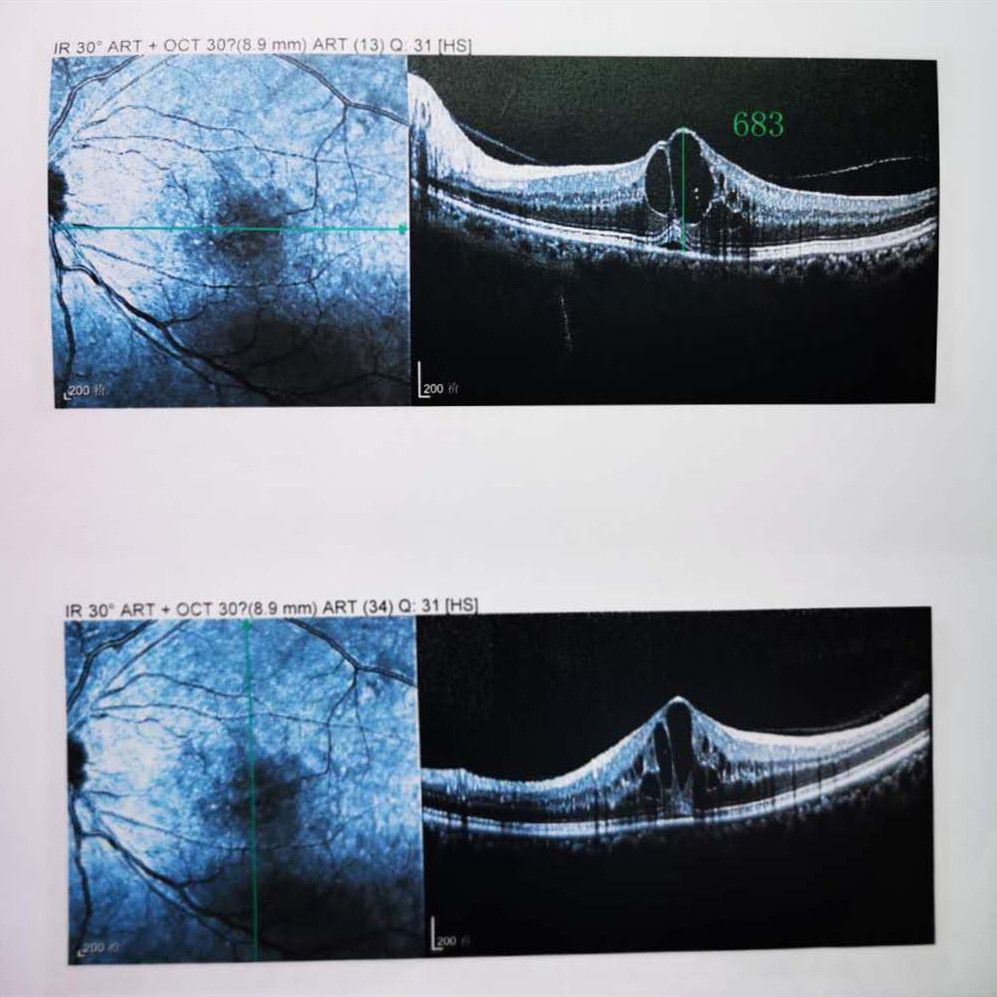

檢查結(jié)果顯示,武先生并沒有近視,右眼視力為1.0,但是左眼視力只有0.4,而且左眼視網(wǎng)膜各分支靜脈迂曲擴(kuò)張,全網(wǎng)膜面見火焰狀出血,黃斑區(qū)高度水腫、滲出,黃斑中心凹厚度約683um。

(武先生初次就診眼底OCT檢查圖)

而正常的矯正視力是1.0,黃斑中心凹厚度在200um左右。

“你這黃斑都腫到正常人的三四倍大了!”廈門眼科中心吳國基院長醫(yī)生告訴武先生,“你這是左眼視網(wǎng)膜中央靜脈阻塞伴黃斑水腫,你左眼的視力下降、看東西變形,是因為你左眼視網(wǎng)膜的中央靜脈發(fā)生了阻塞、出血,導(dǎo)致眼底黃斑水腫了。”

那么,武先生的視力恢復(fù)情況如何呢?幸運(yùn)的是,經(jīng)過兩次玻璃體腔注藥術(shù),武先生左眼的黃斑水腫得到明顯改善,視力已經(jīng)恢復(fù)到0.8。

(武先生出院時眼底OCT檢查圖)